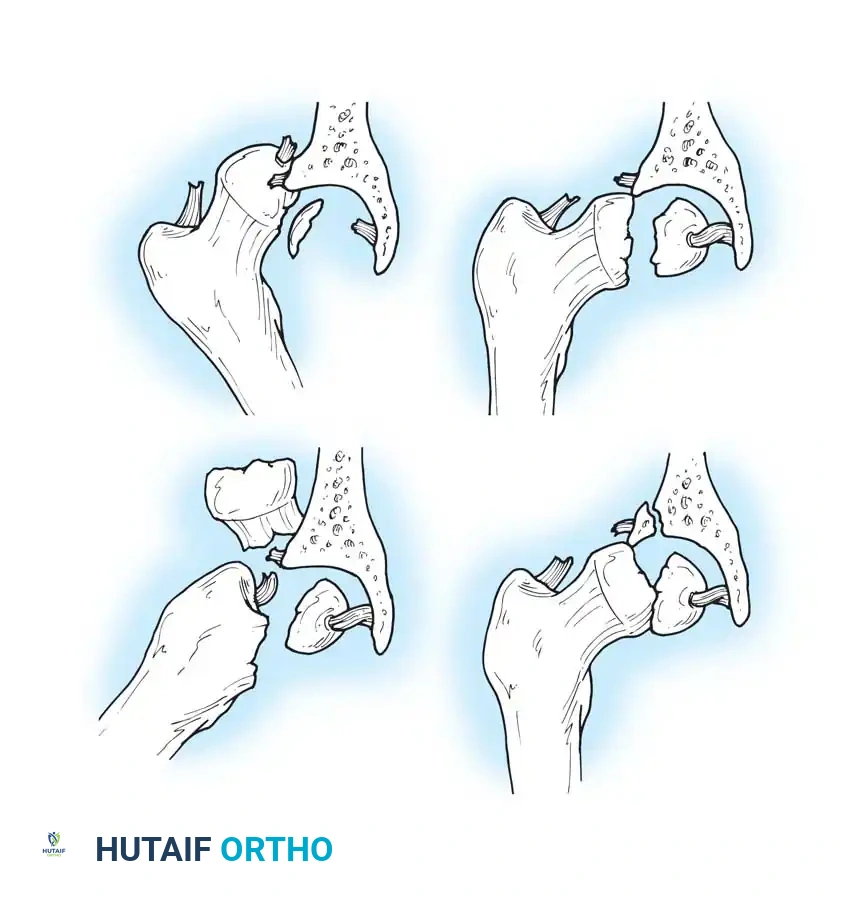

Thompson and Epstein Classification

For posterior dislocations, the Thompson and Epstein classification remains a foundational framework, dividing these injuries into five distinct types:

- Type I: Dislocation with or without a minor fracture.

- Type II: Dislocation with a large single fracture of the posterior acetabular rim.

- Type III: Dislocation with comminution of the posterior acetabular rim, with or without a major fragment.

- Type IV: Dislocation with fracture of the acetabular floor.

- Type V: Dislocation with fracture of the femoral head.

Diagrammatic representation of various hip fracture-dislocation patterns highlighting the relationship between the femoral head and acetabular rim.

Further classification of femoral head fractures associated with posterior hip dislocations, emphasizing the location of the fracture relative to the fovea capitis.

While this classification system was formulated before the widespread advent of Computed Tomography (CT), it remains conceptually vital. Historically, Thompson and Epstein recommended routine open reduction for all fracture-dislocations to clear retained fragments. Today, high-resolution CT allows for precise preoperative identification of retained osteocartilaginous fragments, guiding the decision between closed management and operative intervention.